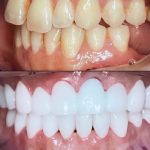

Bir necha yil davomida tish muammolari bilan qiynaldim, lekin bu klinikadagi shifokorlar mening barcha muammolarimni hal qilishdi. Hozir tabassumimni hech narsadan tortinmasdan namoyish etaman. Ular chinakamiga mijozlariga g'amxo'rlik qilishadi. Rahmat!

Men doim stomatologiya muolajalaridan biroz qo'rqardim, lekin bu klinikada hamma narsa o'zgardi! Xodimlar juda samimiy va tajribali. Davolanishning har bir bosqichida o'zimni juda qulay his qildim. Endi tishlarim butunlay sog'lom va go'zal! Bu yerdan xizmat olganimdan juda mamnunman.

Men tish implantatsiyasi xizmatidan foydalandim va natijalardan hayratdaman. Davolanish jarayoni muammosiz o'tdi va shifokorlar har bir bosqichda menga to'liq tushuntirishlar berib turishdi. Endi tishlarim nafaqat tabiiy ko'rinishga ega, balki o'zimni ancha ishonchli his qilaman. Tavsiya qilaman!

Tish implantatsiyasiga qaror qilish biroz qiyin edi, lekin bu klinika menga to'liq ishonch bag'ishladi. Shifokorlar juda mehribon va tajribali, implantlar juda qulay va tabiiy ko'rinadi. Men juda mamnunman va do'stlarimga ham tavsiya qildim.

Tish muolajalarini bu klinikada olganimdan keyin endi boshqa joy qidirmayman. Shifokorlar ishlarini juda aniq va professional tarzda bajarishdi. Davolanish jarayoni doimiy e’tibor va ehtiyotkorlik bilan amalga oshirildi. Juda minnatdorman!

Tish implantlari haqida juda ko'p yaxshi eshitganman, lekin bu klinikadagi natijalar barcha kutilganlardan oshib ketdi! Davolanish jarayoni juda yumshoq o'tdi va natijalardan juda mamnunman. Barcha xodimlar juda malakali va g'amxo'r edi. Rahmat!